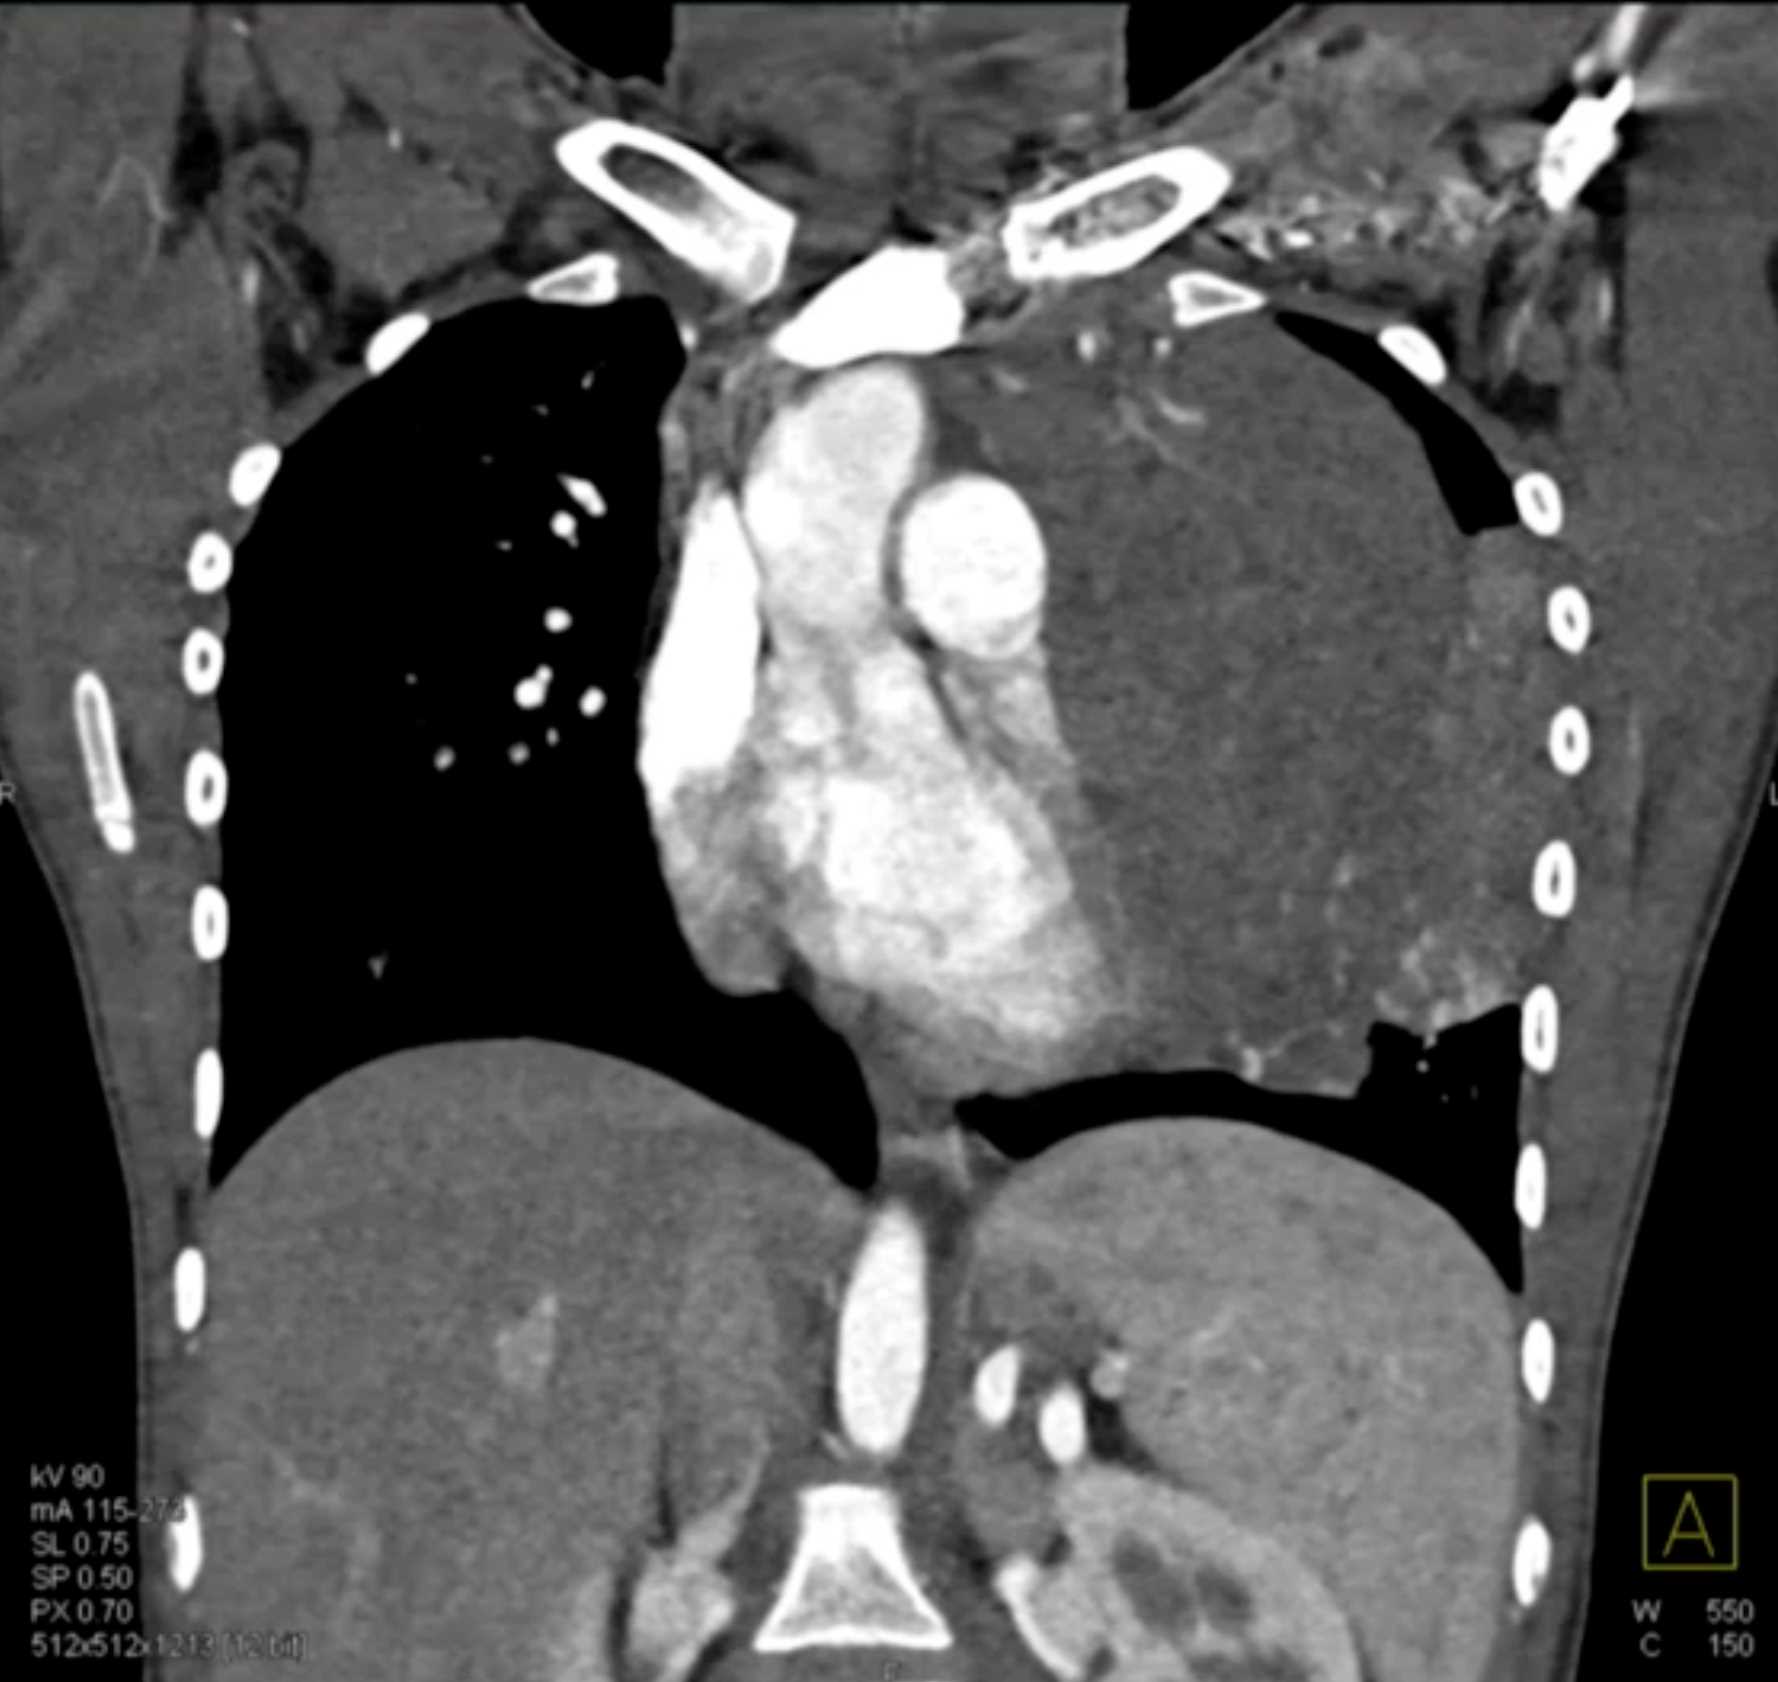

Subtle Adenocarcinoma Pancreas